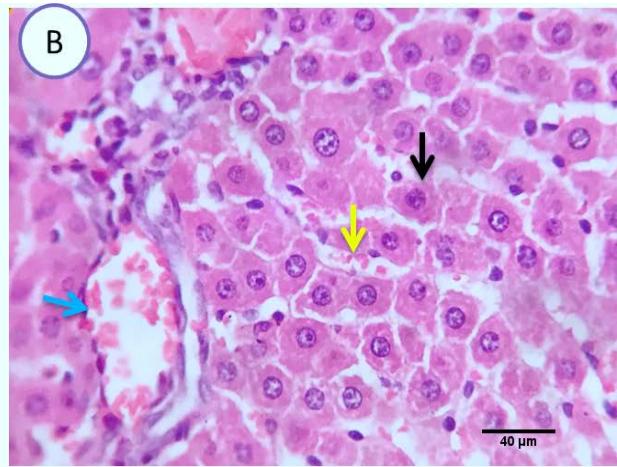

Liver: Examined serial sections denoted apparently normal hepatic parenchyma, lobular arrangement, portal triads structures, vascular tributaries and biliary tree, however some sections showed vascular dilatation and mild portal round cells aggregation. (Fig.4).

Fig. 2: Photomicrograph of liver (Group.G) showing normal hepatic parenchyma(blue arrows), vascular dilatation(yellow arrows)and mild portal round cells aggregation(black arrows). Scale bars 60, 80 um